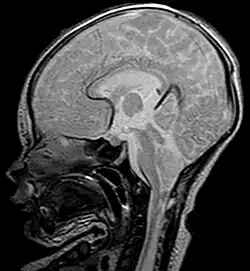

Als Chiari-Malformation wird eine Gruppe von Entwicklungsstörungen mit Verschiebung von Kleinhirnanteilen durch das Hinterhauptloch (Foramen magnum) in den Spinalkanal bei gleichzeitig bestehender verkleinerter hinterer Schädelgrube bezeichnet. Namensgeber ist der Pathologe Hans Chiari (1851–1916), der diese Störung erstmals beschrieb.[1] Die Bezeichnungen Arnold-Chiari-Malformation und Arnold-Chiari-Syndrom wurden von den Schülern des Pathologen Julius Arnold (1835–1915) propagiert, scheinen aber nicht gerechtfertigt, weil diese Gruppe der Entwicklungsstörungen von Arnold nur oberflächlich beschrieben wurde.[2]

Die Diagnosestellung erfolgt kernspintomographisch. Bei Feten können das so genannte Lemon sign oder Banana sign als sonografische Softmarker in der pränataldiagnostischen Sonografie ein möglicher Hinweis auf eine Chiari-Malformation sein.